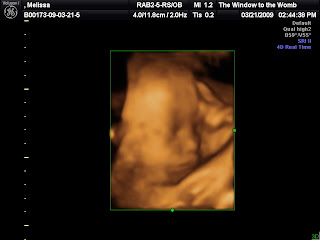

Over the weekend Ed and I went to get some 3D/4D ultrasound photos. It's amazing what they can do these days. We confirmed that our little girl is definitely a girl! While we were looking around she was putting on quite a show ... we saw her open and close her mouth, smile several times, open and close her eyes. We also saw that she has a full head of hair and weighs a little over 4lbs. Here are some photos from our visit:

Mouth wide open

Sticking her tongue out

Chubby cheeksSide profile with hand in front of her face Left eye open

SMILE!!